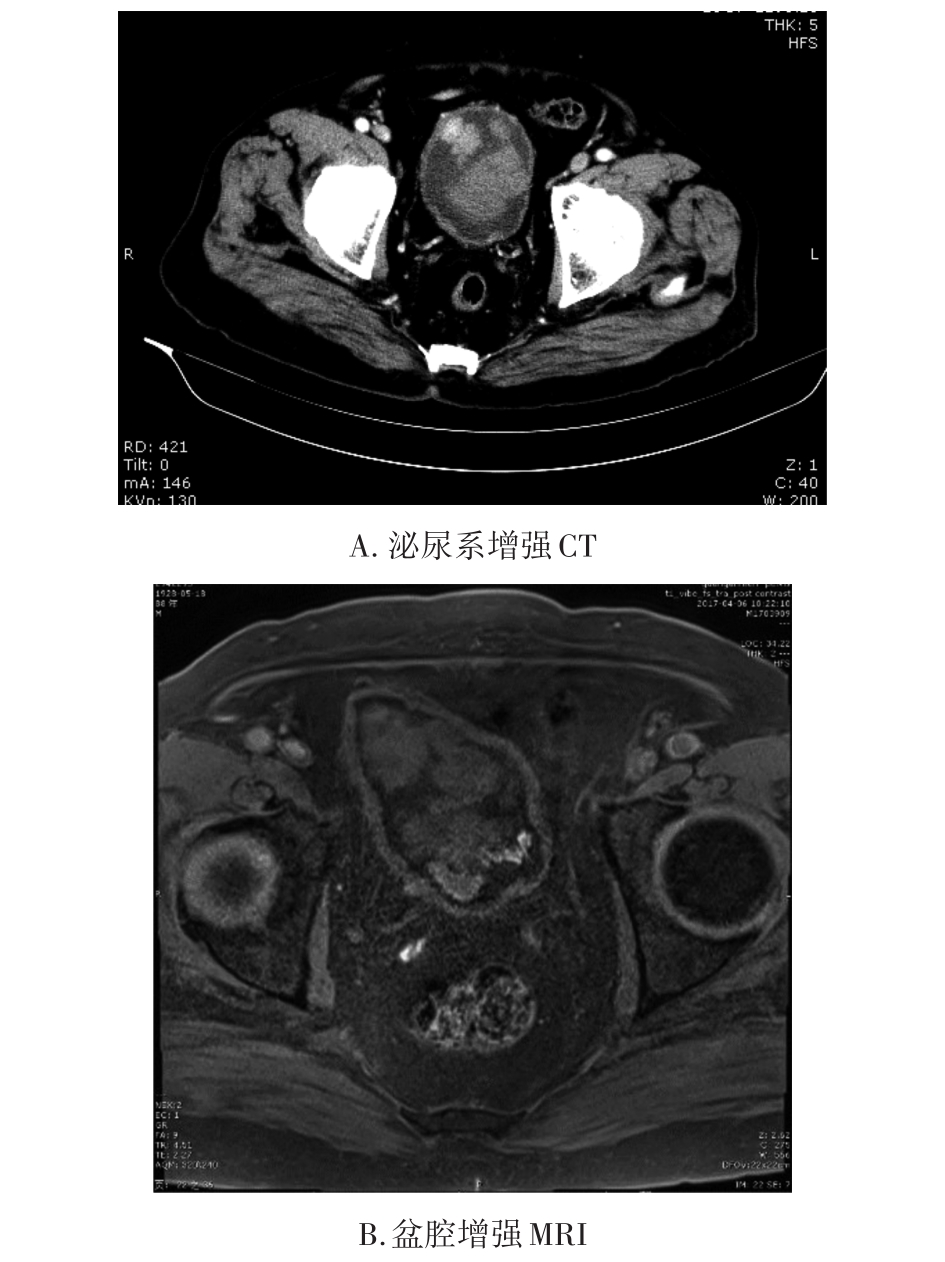

• 转移性上尿路上皮癌在维迪西妥单抗联合替雷利珠单抗新辅助治疗后行根治性肾盂癌切除术1例报道

2023, 48(8):1005-1008. DOI: 10.13406/j.cnki.cyxb.003299

摘要 (52) HTML (36) PDF 2.16 M (1929) 评论 (0) 收藏

摘要: